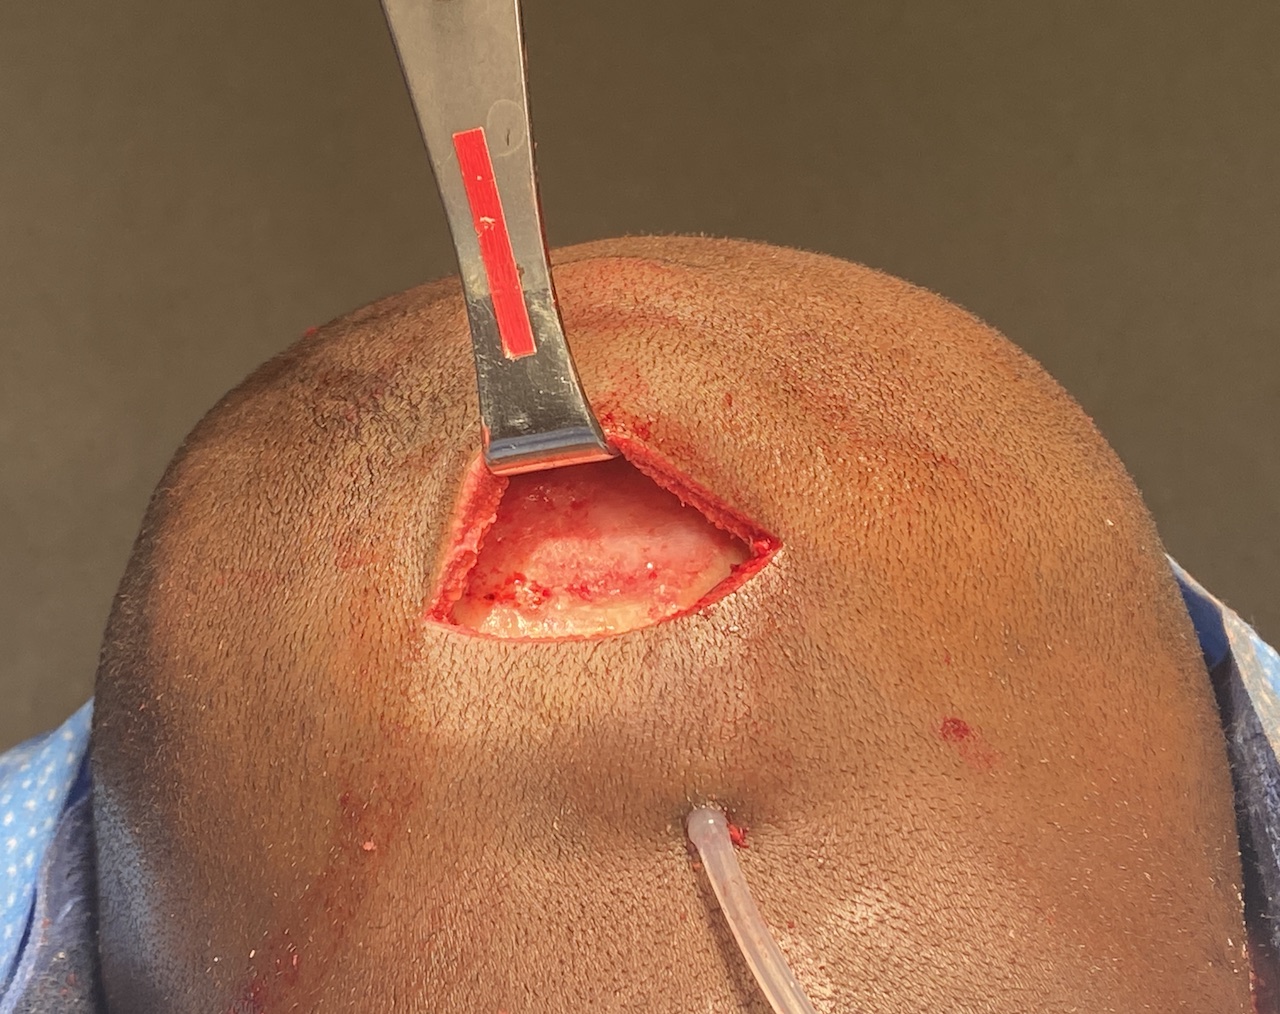

Desire for reduction of prominent occipital knob deformity.

Intraoperative result from occipital knob skull reduction through a direct small scalp incision.